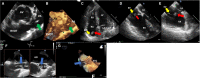

Compared with the extensive data on left-sided infective endocarditis (IE), there is much less published information on the features and management of right-sided IE. Right-sided IE accounts for 5% to 10% of all IE cases, and compared with left-sided IE, it is more often associated with intravenous drug use, intracardiac devices, and central venous catheters, all of which has become more prevalent over the past 20 years. In this manuscript on right-sided IE we provide an up-to-date overview on the epidemiology, etiology, microbiology, potential locations of infection in the right heart, diagnosis, imaging, common complications, management, and prognosis. We present updated information on the treatment of pacemaker and device infections, infected fibrin sheaths that appear to be an easily missed source of infection after central line as well as pacemaker removal. We review current data on the AngioVac percutaneous aspiration device, which can obviate the need for surgery in patients with infected pacemaker leads and fibrin sheaths. We also focused on advanced diagnostic modalities, such as positron emission tomography/computed tomography. All of these are supported by specific case examples with detailed echocardiographic imaging from our experience.